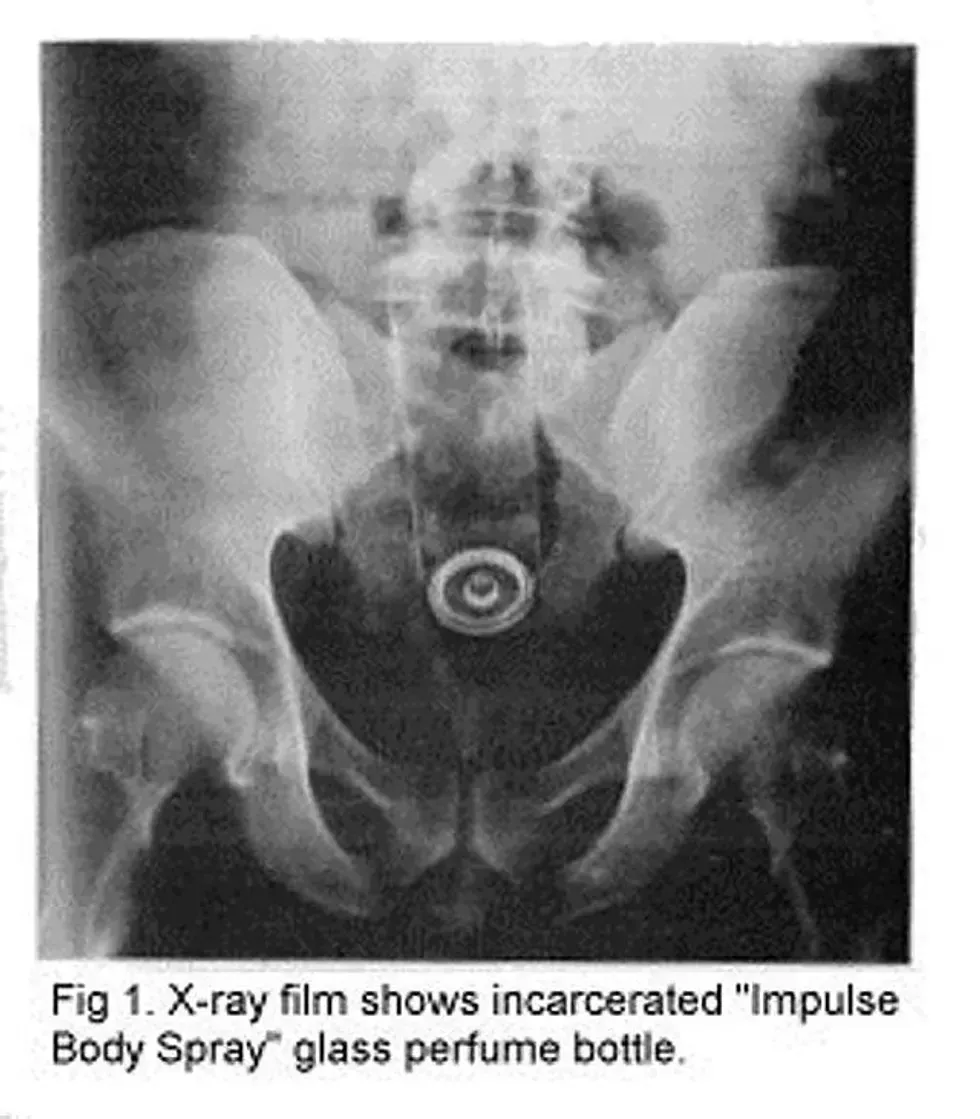

21. A body spray canister